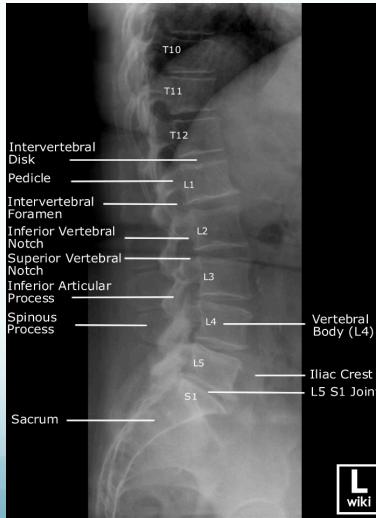

Radiographic (X-Ray) Views

- Standard Views: AP (Anteroposterior), LAT (Lateral)

- Specialized Views:

- LAT Flexion-Extension: To diagnose instability (especially in lower back pain)